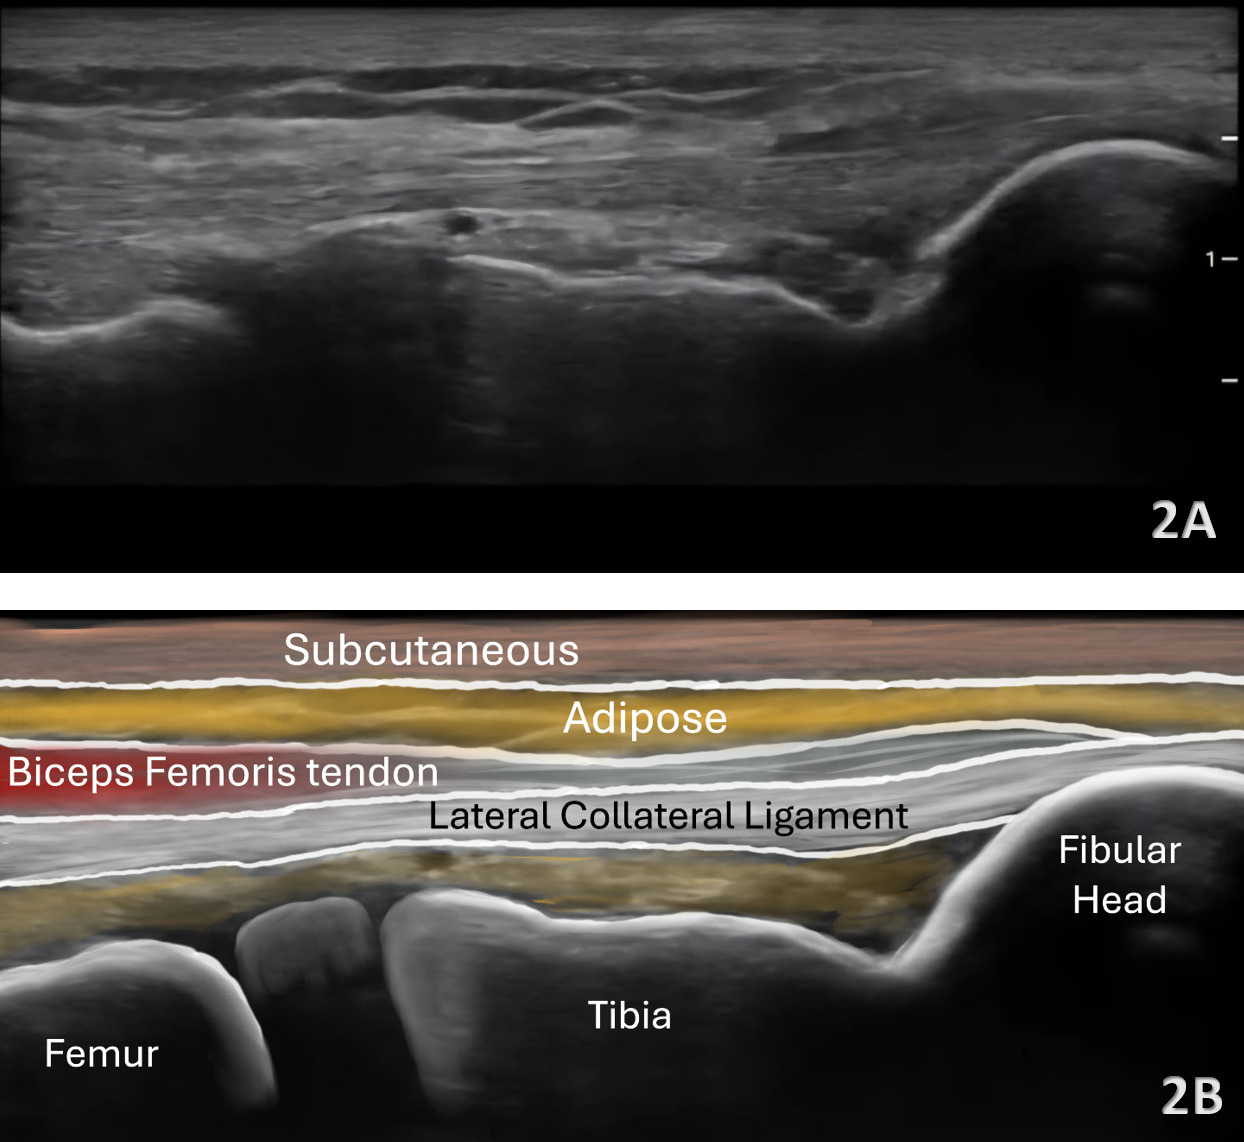

Patient Position: The patient is supine with the hip internally rotated and the knee in slight flexion (35-40 degrees). A bolster or towel roll can be placed under the medial knee for support. The probe is placed in either the short axis (SAX) or longitudinal axis (LAX), starting proximally near the lateral femoral epicondyle or distally at the fibular head.

Normal Sonographic Appearance

In the LAX view, depending on the probe width and size, one should start distally to visualize the hyperechoic reflection of the bony cortex of the fibular head distally and the cortex of the femoral epicondyle more proximally. If the depth is increased enough, you will also be able to visualize the bony reflection of the tibia directly below the fibular head. Usually, the LCL demonstrates a hyperechoic fibrillar pattern. The distal portion of the tendon may appear heterogeneous and thickened due to the bifurcating distal biceps femoris tendon that runs both superficial and deep to the LCL.9